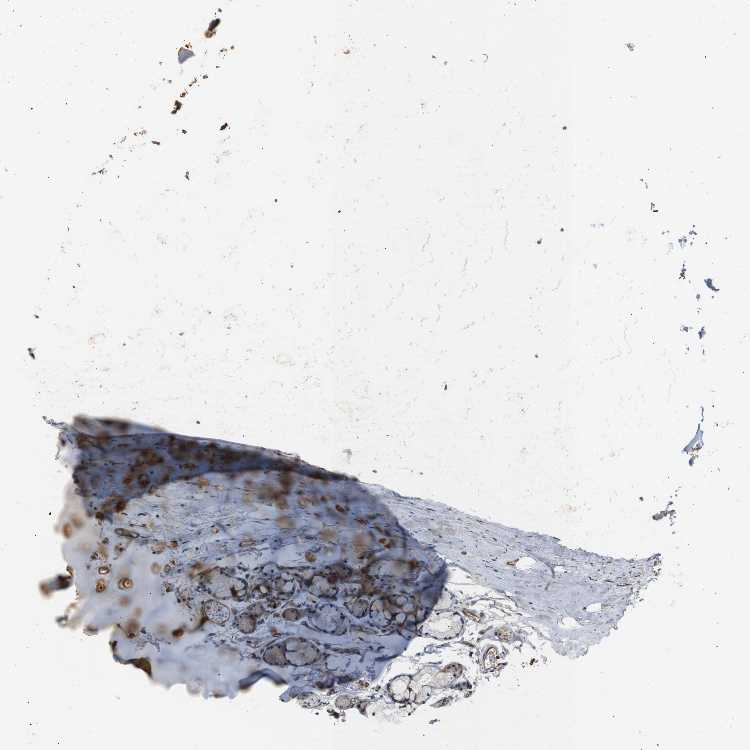

SOFT TISSUE 1 - Antibody stainingi

Antibody staining in the annotated cell types in the current human tissue is reported as not detected, low, medium, or high, based on conventional immunohistochemistry profiling in selected tissues. This score is based on the combination of the staining intensity and fraction of stained cells.

Each image is clickable and will lead to virtual microscopy that enables deeper exploration of all samples and also displays staining intensity scores, fraction scores and subcellular localization as well as patient and tissue information for each sample.

Antibody CAB013514

Chondrocytes Medium

Fibroblasts Medium

Peripheral nerve Low